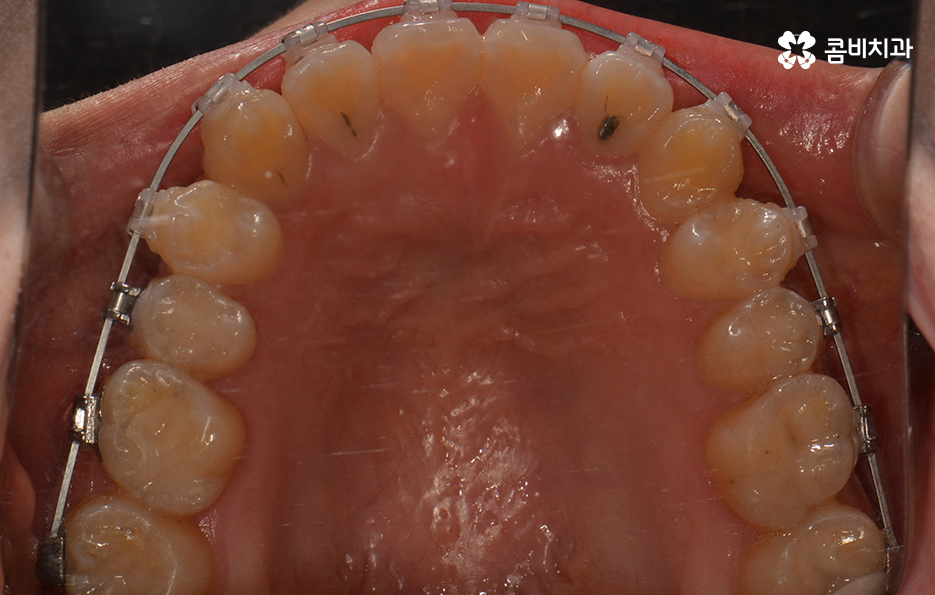

위 환자분의 경우에는 비발치로 송곳니 덧니 교정이

진행된 사례이며 전체 진료 기간은 약 1년 6개월가량이 소요되었습니다.

클리피씨 교정을 통해서 덧니가 개선되고 있는 경과

앞서 치아교정에 걸리는 기간은 어떤 교정 장치를 선택하냐에

따라서 차이가 발생된다고 말씀을 드렸는데요.

요즘 선호도가 높은 교정 장치로는 클리피씨 교정이 대표적입니다.